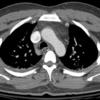

Nl Fat 1a

Date: 04/17/2005

Views: 4126